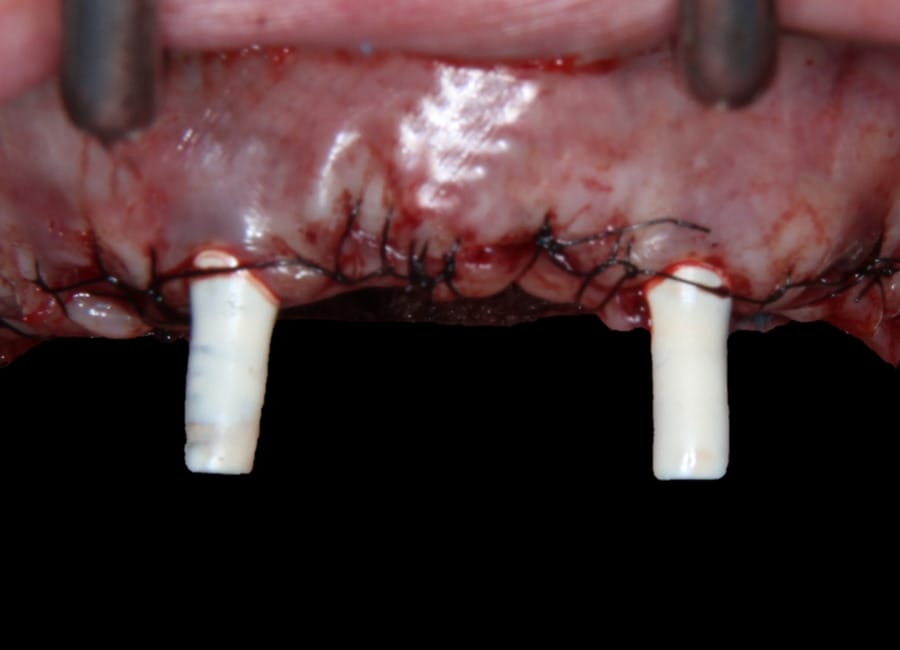

Surgical phase

Natalie’s treatment began with a comprehensive clinical assessment, including a review of her medical and dental history, a full examination, and analysis of her functional difficulties such as her tongue habit and altered bite. A 3D cone-beam CT scan was then taken to assess bone quality and volume, identify areas of infection, and map important anatomical structures to ensure safe implant placement.

All data were transferred into digital treatment planning software, allowing virtual placement of implants and collaboration with the dental laboratory before surgery. This enabled careful evaluation of long-term outcomes and ensured the design of provisional and final prosthetics could be completed with precision. Following these discussions, the decision was made to proceed with the Fixed-Teeth-in-a-Day approach using the All-on-4 technique.